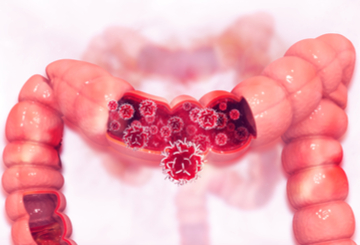

2021年胃肠道肿瘤国际会议(ICGO)

2021年01月18日 罗马